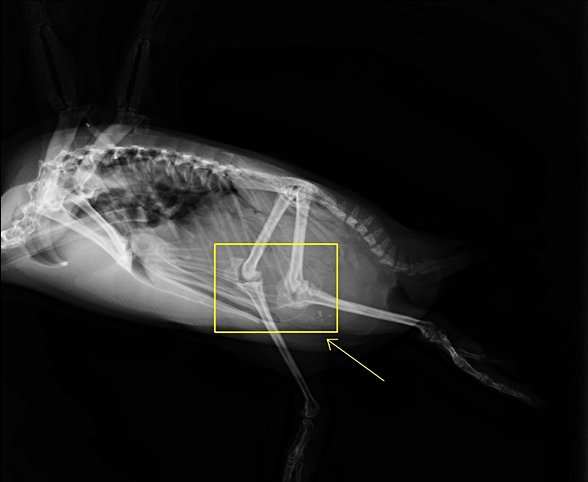

Köpek anatomisine bakalım:

Burada çok ilginç bir şey görüyoruz: Köpeklerde diz çok daha yüksekte, neredeyse karnın içinde. Görselde işaretlenmemiş, ama femur kemiği patella ile "hips" (kalça) arasında kalan kemik. Ayının femuruna göre ne kadar yukarıda olduğunu fark ettiniz mi?

Ayrıca bilek de ("ankle") metatarsalların uzamasına bağlı olarak yükseliyor ve arkadan çıkıntı yapıyor. Yani sizin köpekte "ters diz" sandığınız şey, aslında diz kemiği değil, bilek kemiği. Sadece, köpeklerin karşılaştıkları arazilere ve bu arazilerdeki hareket biçimlerine bağlı olarak evrimsel süreçte metatarsalları uzayıp geriye kaydığı için, yaptıkları çıkıntıyı "ters diz" sanıyorsunuz (daha doğrusu geçici bipedal olan ayılardaki kemik düzeni insana daha benzer, yoksa dört üyelilerde genelde köpeğinkine benzer bir durum görüyoruz).